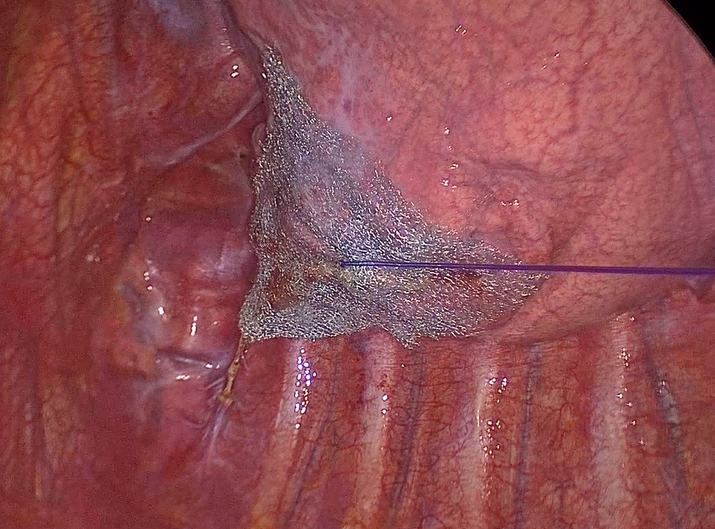

再発の原因として、ブラ切除部や縫縮部の近傍や下葉の頂部に新しいブラができることが知られています。日本国内で実施された全国調査では、原発性自然気胸に対する手術例の約75%で再発予防処置が行われています。その多くは1種類の吸収性シートが用いられていますが、当科ではより術後再発が少ないとされる特徴の異なる2種類の吸収性シートを使った2重カバリング(dual covering)をブラ切除部や縫縮部だけではなく下葉の頂部にも行っています。

PGAシートを縫着

さらに酸化再生セルロース メッシュで被覆

肺尖部と下葉頂部を被覆